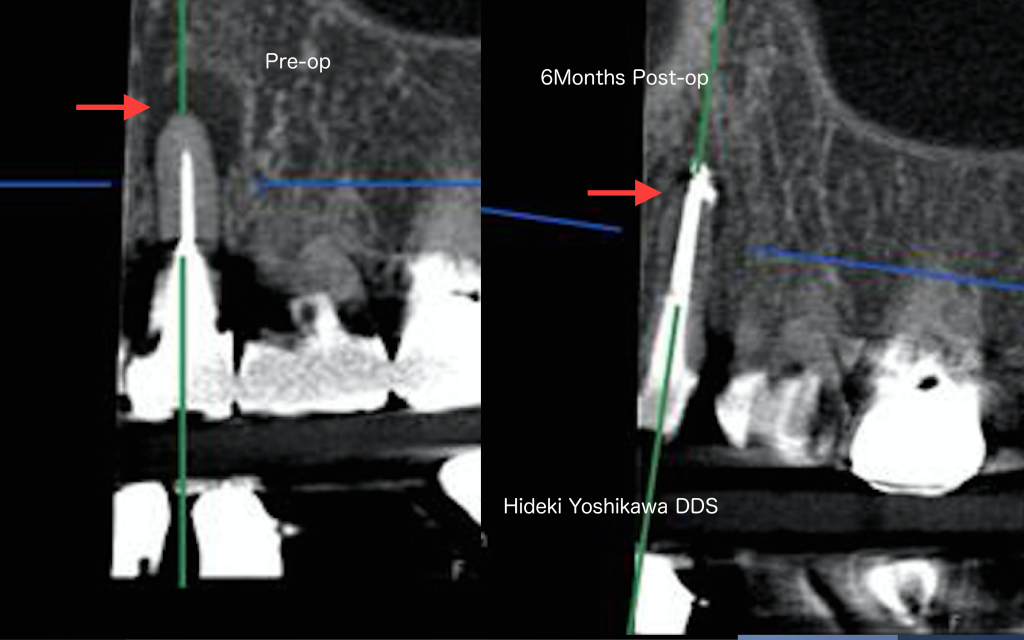

膿が溜まっている歯を根管治療し6ヶ月後のCT像

見事に歯の周囲の炎症は治癒して骨が再生しています。

正しいコンセプトを守った根管治療を行うとこのように治癒致します。

根管充填はMTAセメントで行っています。

MTAセメントとはコンクリートのような組成をもったセメントで組織親和性が高く、水分を持ったところでも硬化出来るセメントで、なおかつ強アルカリの性質があるために多少根管に細菌が残存していたとしてもアルカリ性のために死滅すると言われています。

根管外にMTAセメントが出ていますが、これらの性質のために6ヶ月で驚く程、骨再生を認め治癒しています。